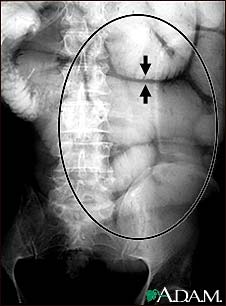

Ileus - X-ray of bowel distension

This abdominal x-ray shows thickening of the bowel wall and swelling (distention) caused by a blockage (obstruction) in the intestines. A solution containing a dye (barium), which is visible on X-ray, was swallowed by the patient (the procedure is known as an upper GI series).